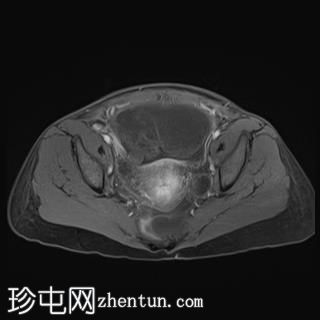

轴位

T2加权像

T2加权像显示复杂囊性肿块,内含出血性物质,右侧卵巢未显影。注意卵巢蒂扭转。

盆腔内可见分层血液成分。